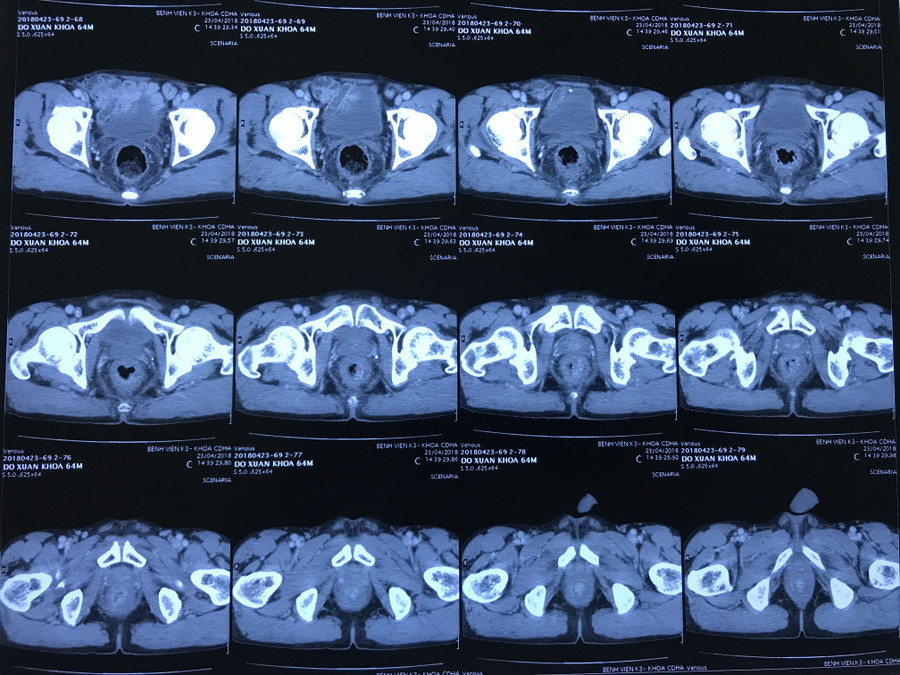

Bệnh nhân đến khám tại bệnh viện K trong tình trạng đau bụng hạ vị, người gầy, cân nặng 45kg, thể trạng già yếu, da xanh, niêm mạc nhợt. Các bác sĩ tiến hành hồi sức tích cực cho bệnh nhân bằng mọi biện pháp: truyền máu, truyền đạm, kháng sinh nâng đỡ cơ thể. Sau khi phục hồi, anh Kh. đã được thăm khám, chụp chiếu và làm các chỉ định, xét nghiệm cần thiết, bệnh nhân được chẩn đoán ung thư trực tràng thấp gây ra thiếu máu, suy nhược cơ thể.

| Phim chụp khối u |